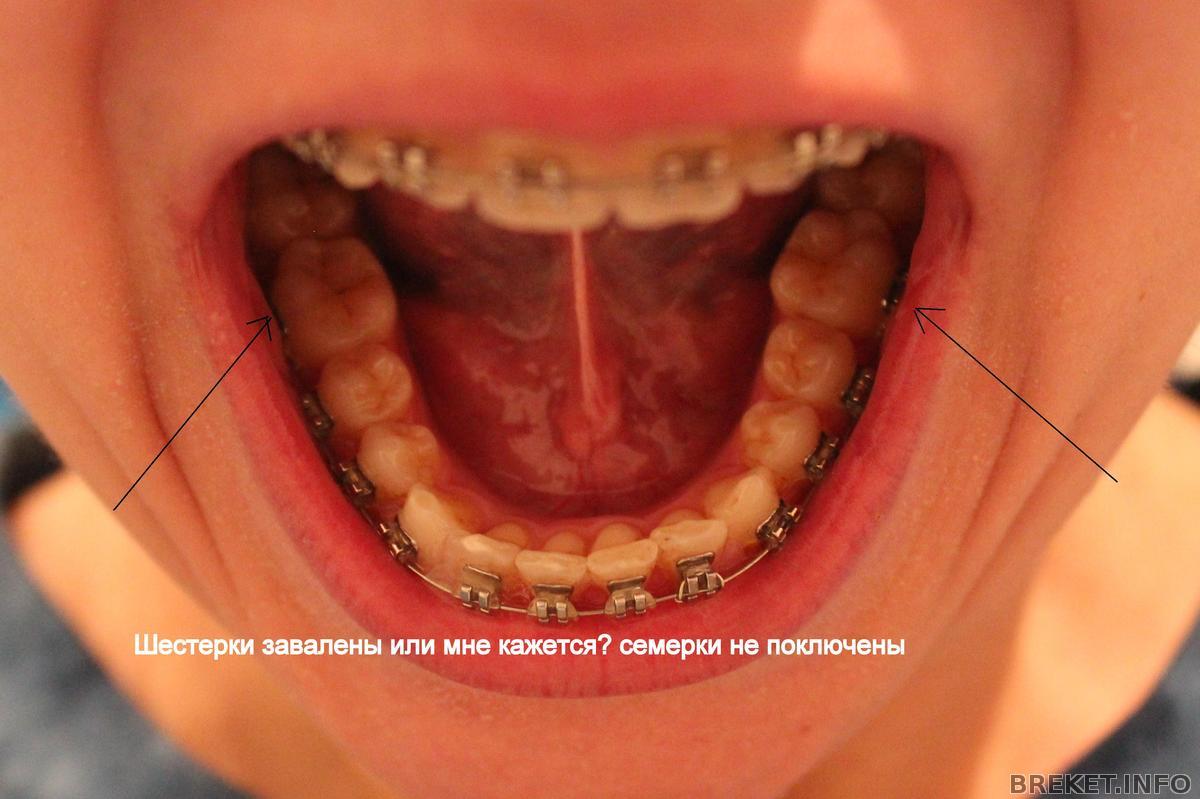

Еще у меня завалены 6ки на нижней челюсти, на что она тоже не обращает внимание. Короче, вопрос, у кого как с этим делом обстоят дела???

Я не увидела заваленных шестерок, они просто сам по себе больше, а ровняют зубы по внешнему краю зубов, а не внутреннему, поэтому, возможно, кажется, что они завалены внутрь. Надеюсь, я понятно донесла свою мысль ![]()

По уму бы, конечно, семерки надо подключать. Но они совсем немного выходят из ряда, это не катастрофично.

Varechka, в идеале, как я себе представляла, что 6ки все-таки должны стоять ровно. Вот даже посмотреть на продемонстрированном коллаже от RaiseHopes. Там с семерками беда, но шестерки внизу хорошо стоят. А у меня вообще нет ровной "подковы". Про центр - конечно, если ровнять верх, то и низ, так как они в тандеме.